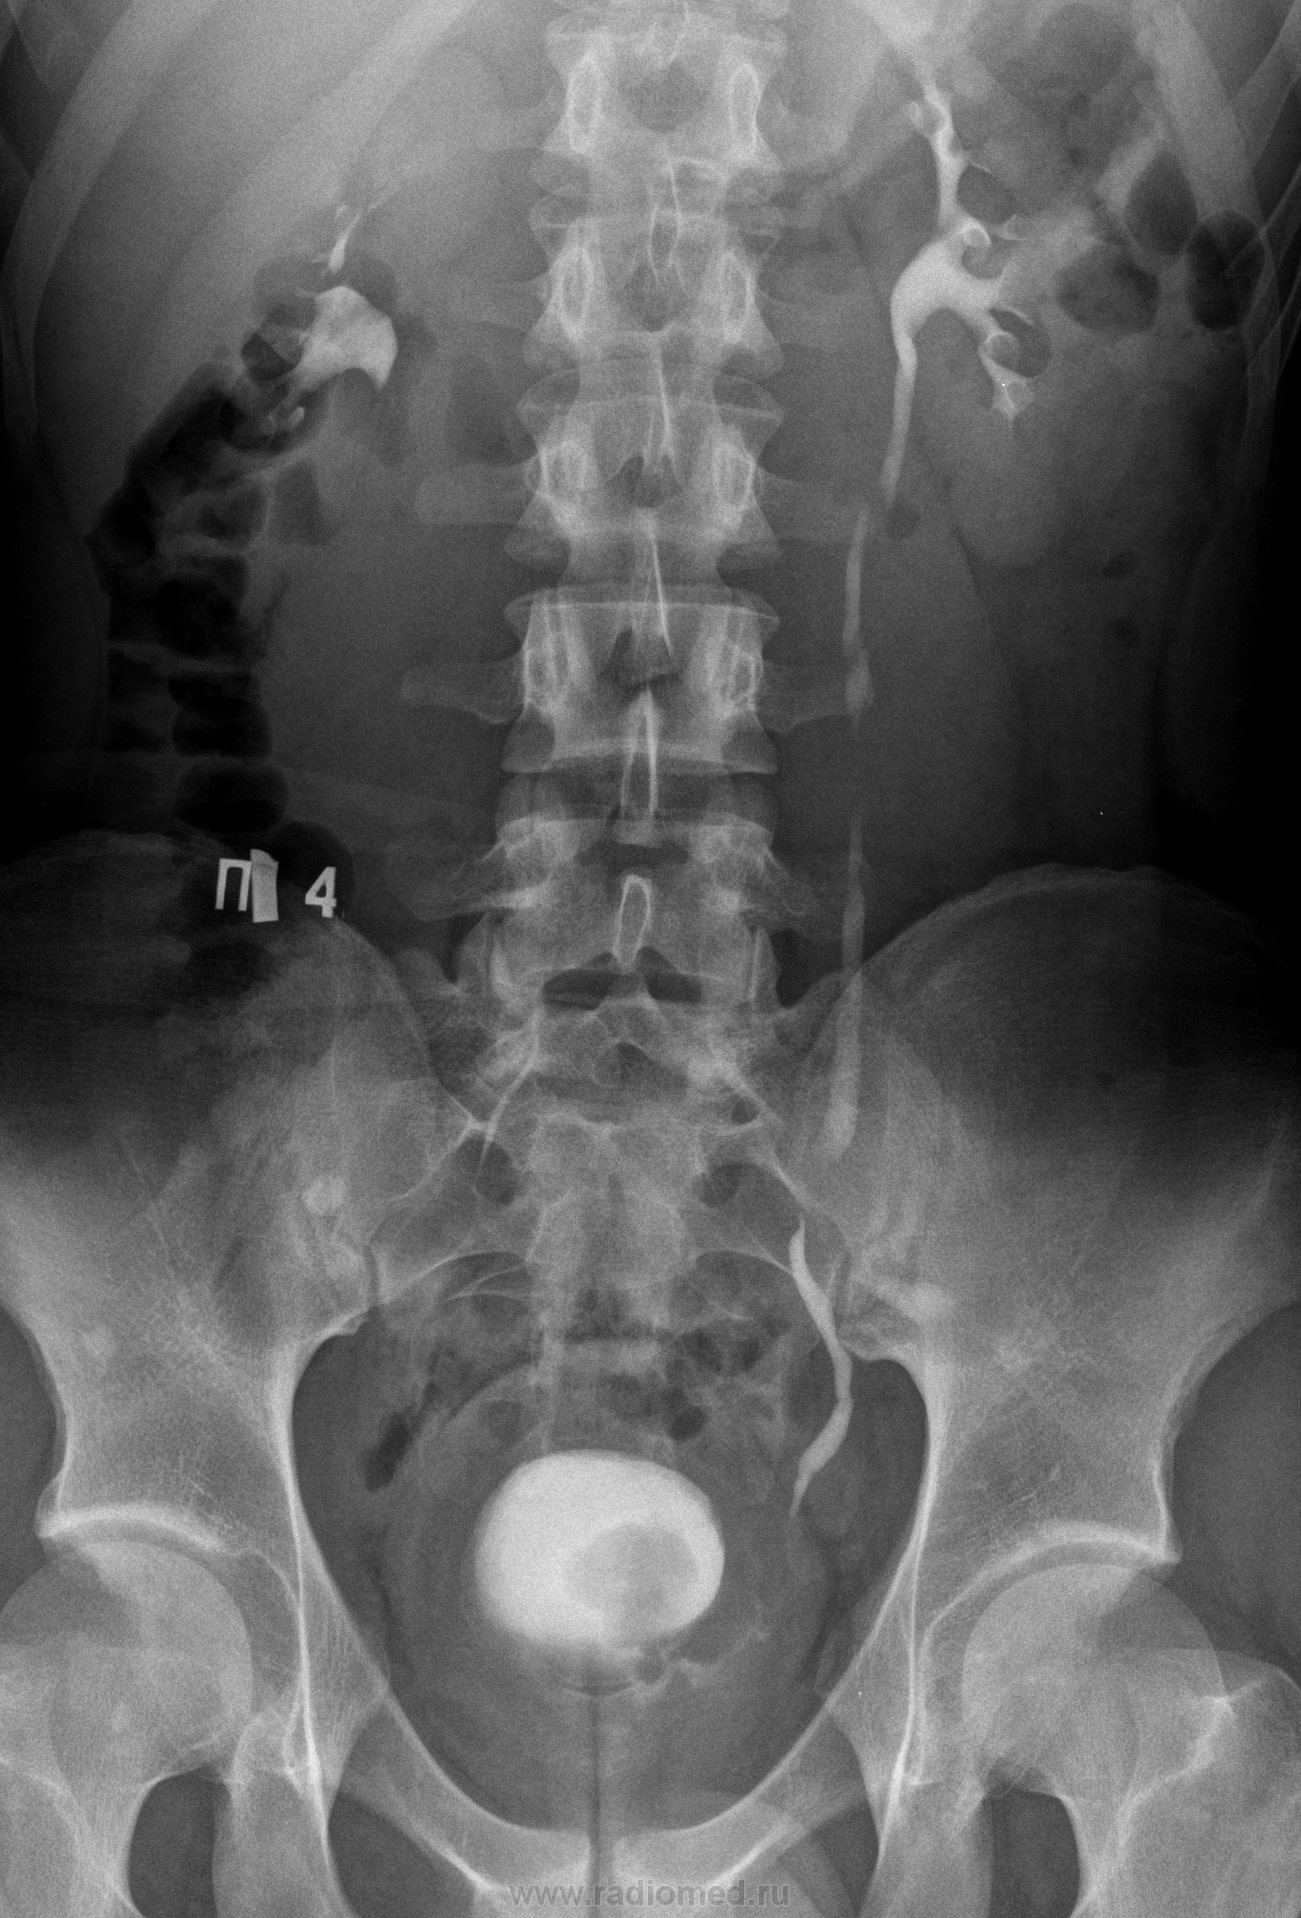

Экскреторная урография.

Молодой человек 17 лет, с повседневными жалобами по поводу дискомфорта во время мочеиспускания.

на четвертой картинке в мочевом пузыре, это дефекты наполнения?а УЗИ проводилось??

В общем- то, дефект заполнения определяется и на 3 снимке, но имеет несколько другую картину, а что это неясно (как часто любят говорить врачи УЗИ: "... мы видим патолгию,... но не знаем что это такое? ...Улыбаюсь", собственно говоря, в этой фразе находит отражение весь тернистый путь ищущего  лучевого диагноста!).

Данному пациенту проводили цистоскопию с биопсией- фиброма мочевого пузыря, после "экскреторки" он был прооперирован.

Патогистологическое исследование

Микроскопическое описание: в материале стенка мочевого пузыря, покрытая гиперплазированным переходным эпителием; с узловым образованием. В строме образования определяются пучки гладкомышечных клеток с эозинофильной цитоплазмой и удлинёнными, мономорфными ядрами, идущие в разных направлениях. Фигуры митоза отсутствует. Между пучками гладкомышечных волокон определяется умеренное количество соединительной ткани. Выражены в строме вторичные изменения: кровоизлияния, очаги гиалиноза, кальцинаты, петрификаты. В подслизистом слое фиброз, отёк, лимфоидная инфильтрация.

Патоморфологическое заключение: лейомиома мочевого пузыря. Хронический цистит. Реактивные изменения слизистой мочевого пузыря: гиперплазия переходного эпителия, фиброз подслизистого слоя.

А, что это за "остеобластические" очаги на фоне тазовых костей?

Чем будем объяснять исчезновение контура поясничной мышцы справа?

Очаги остеопойкелии, думаю имеет место быть восходящего пиелонефрита справа, отмечается каликопиелоэктазия справа.